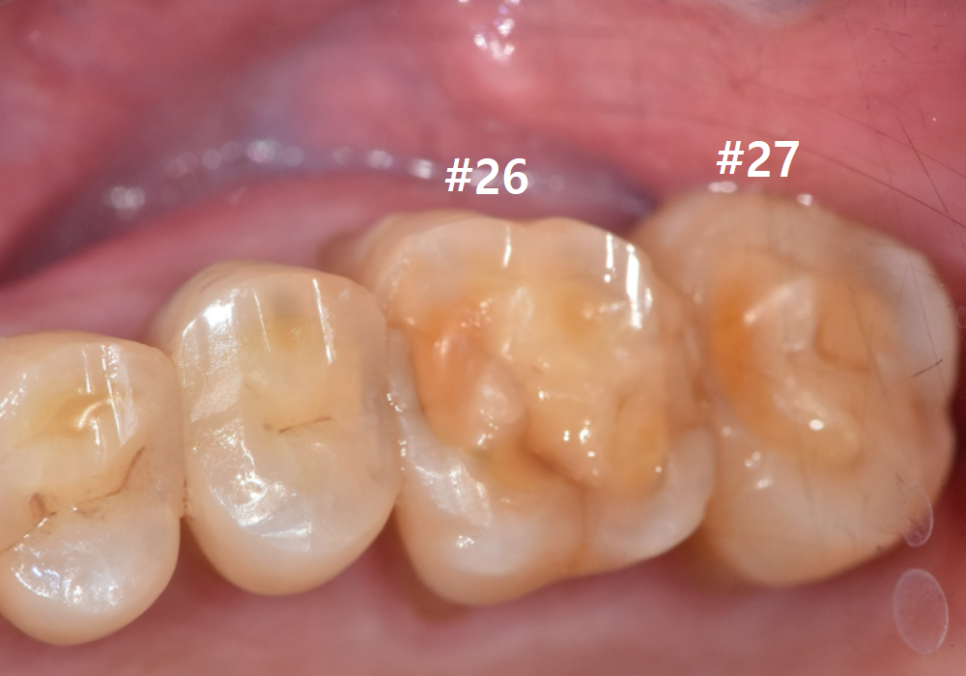

왼쪽 위 어금니 두 개(#26, #27)가 동시에

시큰거려서 내원하셨는데요~

앞쪽 어금니(#26)

: 금이 머리 쪽에만 머무른

'치관 파절'로 예후가 좋아 보였지만,

맨 끝 어금니(#27)

: 금이 뿌리 쪽으로 깊게 내려간

'수직 치근 파절' 상태였습니다.